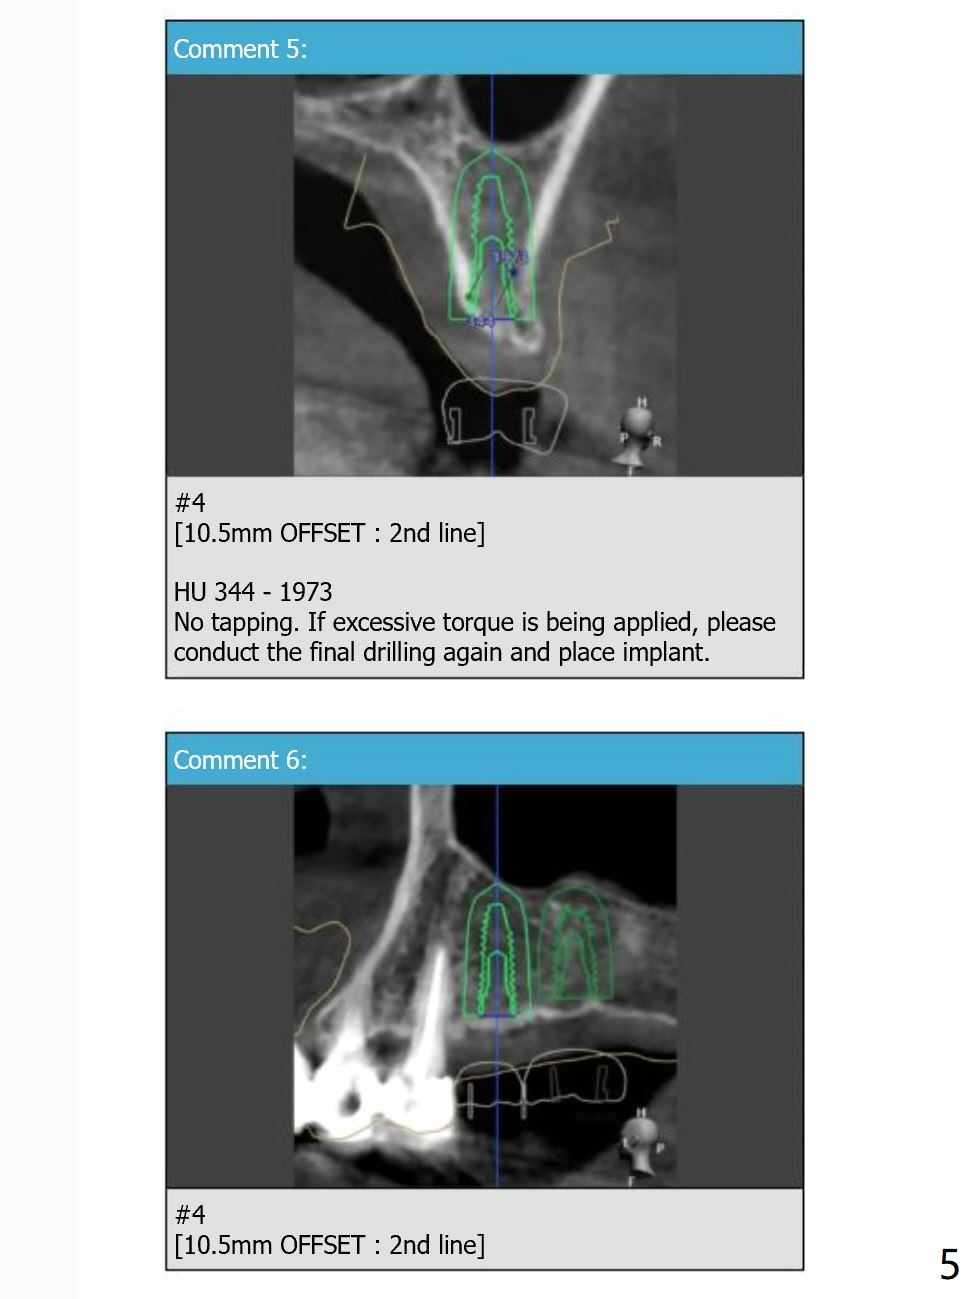

No Tap

Return to Upper Molar Premolar Immediate Implant, Trajectory